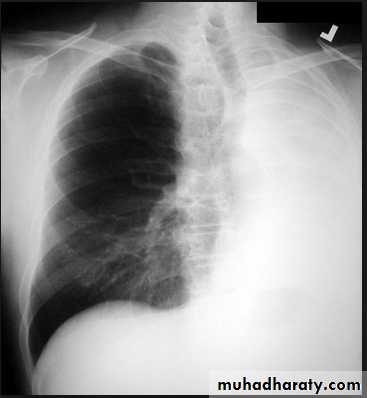

Tension pneumothorax.

On a posteroanterior chest x-ray (A), the left hemithorax is very dark or lucent because the left lung has collapsed completely (white arrows).

The tension pneumothorax can be identified because the mediastinal contents, including the heart, are shifted toward the right, and the left hemidiaphragm is flattened and depressed. A computed tomography scan done on a different patient with a tension pneumothorax (B) shows a completely collapsed right lung (arrows) and shift of the mediastinal contents to the left.